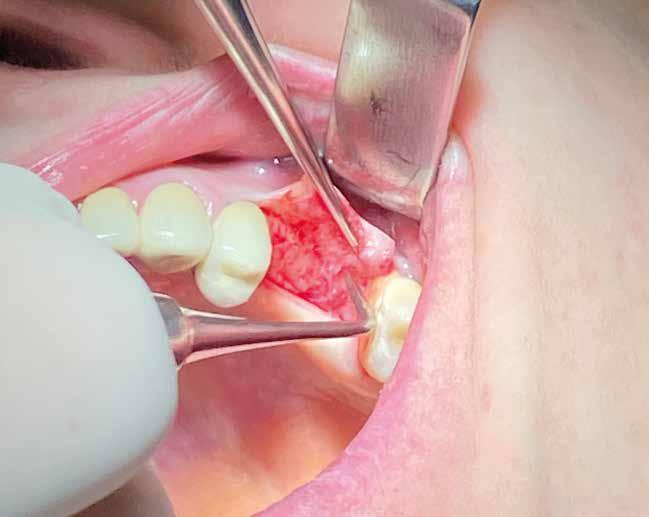

5.2 Accessi chirurgici

Dovendo intervenire sui tessuti molli per raggiungere l’osso sottostante, il chirurgo deve sempre scegliere il lembo più adeguato; un concetto fondamentale è che esso:

ƒ Abbia la dimensione idonea per permettere un’adeguata visuale del sito di intervento.

ƒ Sia il più integro possibile, ossia non presenti incisioni frastagliate, compressioni o danneggiamenti derivanti dalla fase di scollamento.

ƒ Sia disegnato nel rispetto della sede anatomica. È necessario porre estrema attenzione ai tessuti gengivali prossimi ai denti attigui al sito chirurgico, nonché alle strutture nobili circostanti.

Le incisioni di scarico devono essere progettate nel rispetto della vascolarizzazione dei tessuti, cosa che permette di avere una rivascolarizzazione più rapida della zona operata e, di conseguenza, una minor sofferenza dei tessuti in neoformazione. Se i tessuti periferici alla zona di intervento sono meno compromessi (poco ipossici e non frastagliati), è più semplice garantire un sigillo della ferita corretto.

In ultimo, ha grande importanza anche il momento della sutura, la scelta dell’ago, del filo e la tecnica di legatura dei nodi (fatti alla giusta distanza gli uni dagli altri e con la giusta tensione); la riuscita dell’intervento dipende anche dalla qualità con cui vengono riavvicinati i lembi in modo da non ischemizzarne o danneggiarne i bordi. (Figg. 9-14)

Esempio chirurgico di accesso tra 2 elementi dentari con conformazione della cresta alveolare ampia. Incisione del lembo in cre sta senza scarichi laterali con sollevamento di 2 lembi, palatale e vestibolare; si può notare come quest’ultimo non si estenda oltre

Una incisione lineare netta si estende coinvolgendo minimamente il dente mesiale e maggiormente in direzione distale, consente di evitare l’esecuzione di incisioni di scarico che provocano una interruzione della vascolarizzazione maggiore, senza ridurre la visibilità del campo operatorio.

Disegno del lembo d’accesso con spostamento della incisione crestale sul versante palatino. Lo scollamento della porzione vestibolare deve avvenire con uno scollatore di piccole dimensioni e l’ausilio di una pinza chirurgica